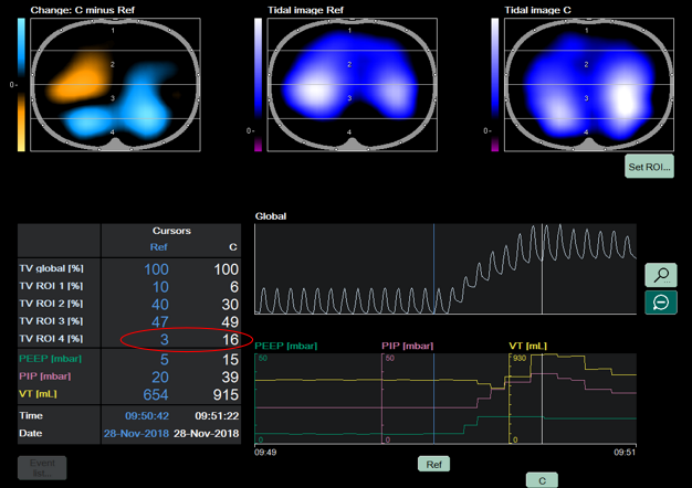

3. 临床监测

1)气胸:能够识别低至20 ml的气胸区域,且敏感性高(图11)

图片

11  EIT识别气胸

2)通气缺损:实时监测单侧肺炎或肺栓塞导致的区域通气下降(图12)

11  EIT识别通气缺损

3)肺大血管栓塞:如果血流缺损,通气也会产生变化,可以据此推断肺血管栓塞可能。

视频2  EIT辅助肺大血管栓塞的诊断和治疗评估

4)肺肿瘤切除术后监测:如图12所示,胸片虽显示肺外观结构未严重毁损,仍有部分肺组织显影,但结合EIT影像可见,部分肺区通气功能近乎丧失,通气功能异常会直接导致氧合水平下降,且随着病情的进展,肺通气障碍若持续加重,氧合恶化将更加显著。通过EIT监测及时发现这类通气异常,并给予针对性干预,可促进肺复张,恢复有效通气。

12  EIT用于肺肿瘤切除术后监测

5)俯卧位通气监测:俯卧位通气在临床中备受关注且展现出显著效果,借助EIT技术可以清晰阐释其作用机制:随着俯卧位通气时间的延长,EIT监测显示肺内气体分布逐渐趋于均匀,同时血流灌注也得到改善(图13)。当气体分布与血流灌注二者协同优化,通气血流比值(V/Q)愈发匹配,呼吸功能随之改善。EIT能够实时、精准捕捉肺内通气与血流的动态变化。

13  俯卧位对患者通气-灌注匹配的影响

图源:Crit Care, 2022, 26(1):154.